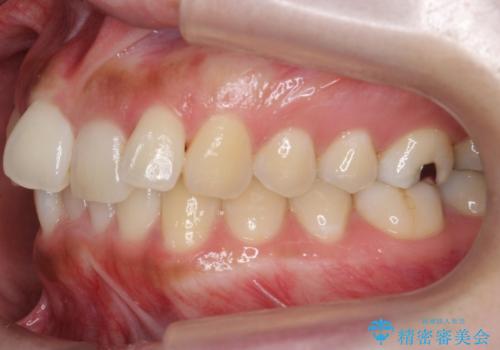

- 前歯のがたつきを主訴に来院。

前歯は目立つのでワイヤー矯正は絶対にしたくないとのことでした。

右上の奥歯を後ろに送り、前歯が出っ歯にならないように並べました。

また、右下の奥歯に一部目立たないように部分的なワイヤー矯正を行い、右下の奥歯が反対咬合になっていたのもしっかり中に入れて治療しています。

奥歯の反対咬合を治すのはインビザラインではかなり難しいのですが、しっかり治療できました。